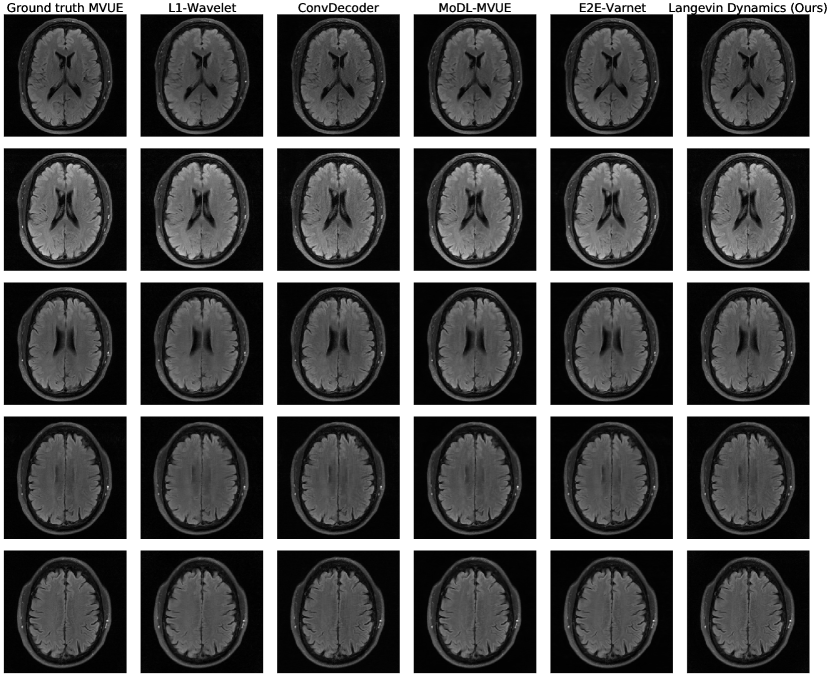

Refer to caption

Figure 3: Comparative reconstructions of a 2D abdominal scan with uniform random under-sampling in the horizontal direction at R=4𝑅4R=4. None of the methods were trained to reconstruct abdomen MRI. Our method uses a score-based generative model trained on brain images (as explained) and obtains good reconstructions. The red arrows indicate missing details or artifacts in the kidney structure.

Figures 2c & 5c show PSNR and SSIM scores obtained on reconstructed abdominal scans obtained from [1] at different acceleration factors. This represents both an anatomy and sampling pattern shift, and it can be seen that our method, MoDL, and the 1subscript1\ell_{1}-Wavelet algorithm retain their competitive advantage, while the ConvDecoder and E2E-VarNet suffer severe performance losses. Figure 3 further shows a qualitative comparison of a reconstructed abdominal scan at R=4𝑅4R=4, with highlighted artifacts. Appendix E shows another abdomen scan.